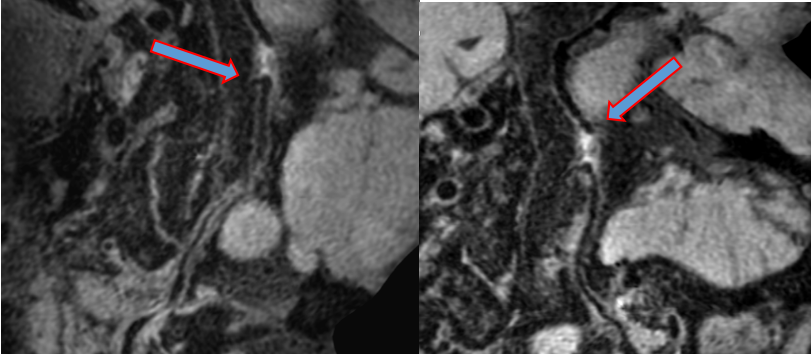

头颅CTA及DSA   脑血管造影显影基底动脉闭塞(箭头所指)

头颅HR--MRA检查,见闭塞段近端远端均有重要分支(箭头所指)